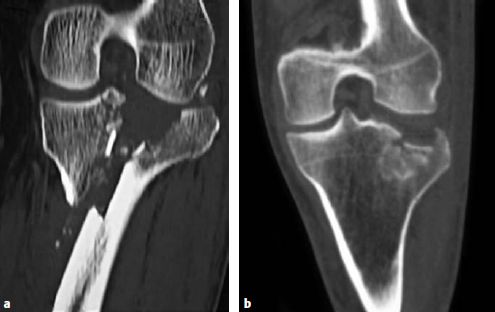

术前CT扫描提供的多个切面以及三维重建已经成为胫骨平台骨折分析的标准工具。CT扫描的时机尽可能选择在进行初始复位并通过石膏或者跨关节外固定架固定后。随着CT技术的发展,骨折的位置及其累及的“柱”受到了越来越多的关注(图6.8.1‑2),有时由于骨折的位置的关系,其损伤范围在X线上难以发现。

图6.8.1-2

后外侧胫骨平台骨折的X线片(a),骨折形态不如CT的轴位(b), 冠状位(c)和三维重建(d)那么清楚。